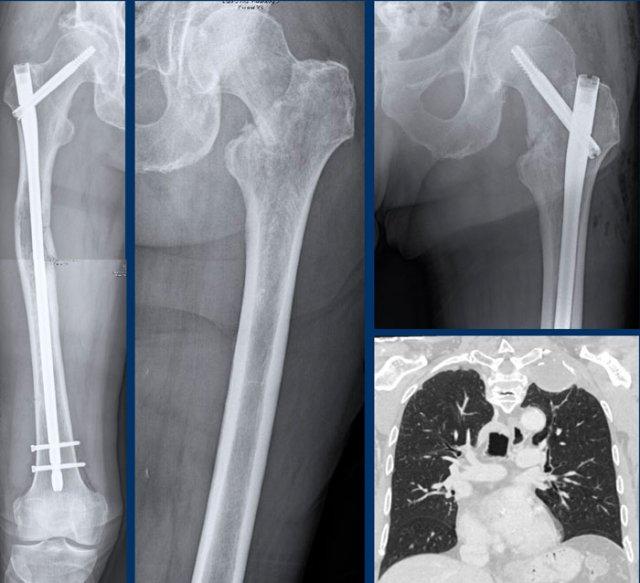

Continue with the postoperative

X-rays…..

Điều trị bao gồm cắt bỏ khối xương đùi gần và tái tạo bằng nội khớp giả.

Pathology confirmed a chondrosarcoma grade II.

Chondrosarcoma độ II và độ III không thể phân biệt dựa trên hình ảnh học.

Đây là chẩn đoán được thực hiện dựa trên mô bệnh học.

Do đó, chúng tôi gọi các tổn thương như vậy là “độ II hoặc cao hơn” trong báo cáo chẩn đoán hình ảnh của chúng tôi.